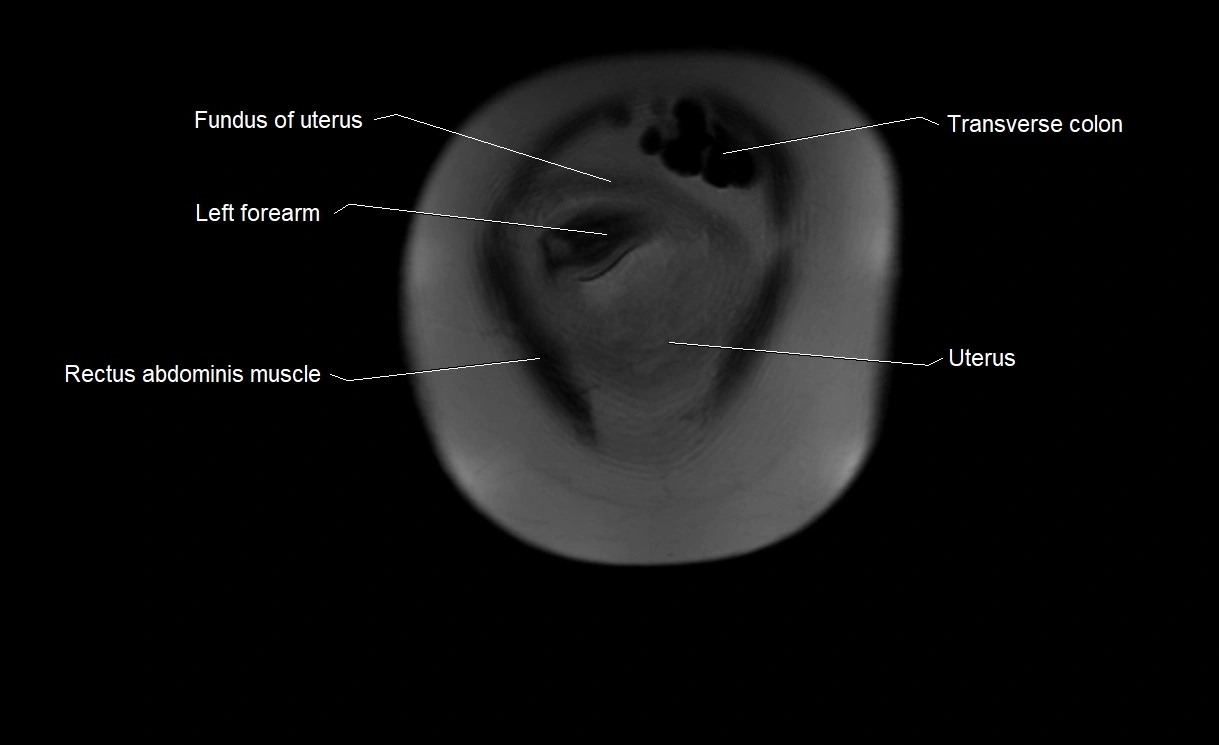

Relations

• Enclosed within the amniotic sac, bounded by the amnion and chorion

• Surrounds and cushions the developing fetus

• In continuity with maternal circulation through placental and transmembrane exchanges